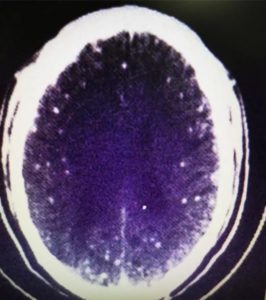

Se você é fã de carne de porco, o caso do chinês Zhu Zhongfa talvez torne você ainda mais exigente quando o assunto é o bom preparo desse alimento. Isso porque mais de 700 ovos de tênia foram encontrados no cérebro do homem, após ele ingerir um caldo com carne mal cozida.

Segundo os médicos de Zhu, o paciente de 46 anos foi parar no Hospital da Universidade de Zhejiang, no leste da China, apresentando graves convulsões, que se assemelhavam a um quadro de epilepsia. Ele já havia sido hospitalizado antes, com tontura e forte dor de cabeça, mas recusara qualquer tipo de tratamento por não querer gastar dinheiro.

Como o cérebro humano é muito vascularizado, os animais costumam se instalar por lá. Ainda assim, outras regiões também estão em risco: o próprio Zhu apresentou infestação nos pulmões.